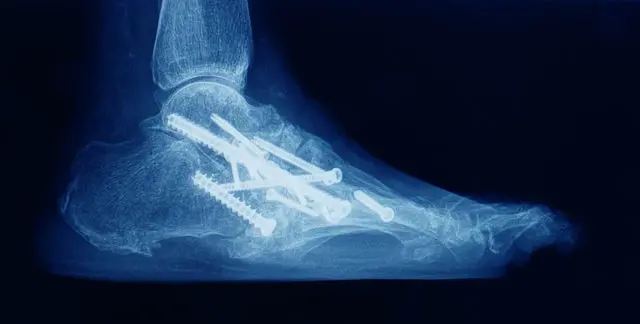

Fixation options

-

Multiple large-diameter screws (often 2-3)

Plate + screws constructs (especially anterior plating)

Hybrid screw + plate designs

Supplemental external fixation in challenging cases

Bone grafting (autograft / allograft / bone substitutes) where defects exist

Bone Alignment: The tibia and talus bones are positioned in a natural alignment.

Fixation: Screws, plates, or rods are used to hold the bones together.

Closure: The incision is closed with sutures, and a sterile dressing is applied.